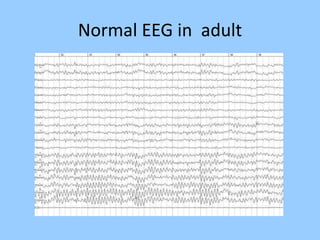

3. International standards for EEG electrode placement and recording parameters are reviewed. Characteristics of different EEG waves, amplitudes, and patterns are described.